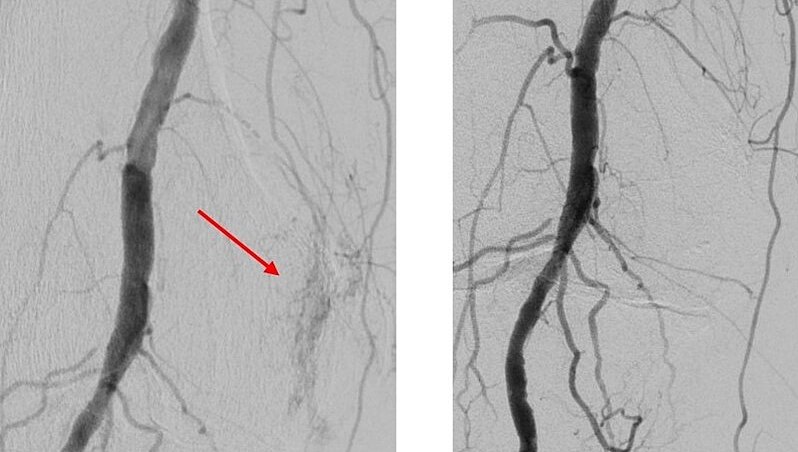

Gefäßeröffnende Therapie bei arteriellen und venösen Durchblutungsstörungen

Die Behandlung verengter oder verschlossener Blutgefäße - mit Ausnahme des Herzens - macht einen Großteil der bei uns durchgeführten Eingriffe aus. Dazu zählt die Therapie der peripheren arteriellen Verschlusskrankheit (Schaufenstererkrankung), Nierenarterienstenosen oder Engstellen der darmversorgenden Gefäße. Ein weiterer Teilbereich ist die Behandlung von Komplikationen bei Dialyseshunts.

Hierbei kommen verschiedenste hochmoderne Techniken zum Einsatz. Diese beinhalten die Aufdehnung von Engstellen mit einem Ballonkatheter oder die Stentimplantation (Angioplastie), das Absaugen von Thromben (Aspirationsthrombektomie), aber auch weitere hochspezifische Verfahren wie z.B. die Verwendung von „Gefäßfräßen“ (sog. Atherektomie) oder auch der Einsatz von Stoßwellen (Lithoplastie). Auch venöse Engstellen oder Gefäßverschlüsse können unter Einsatz endovaskulärer Techniken behandelt werden. Hierzu zählen zum Beispiel tumorbedingte Einengungen der großen Hohlvene oder auch Thrombosen.

Die Behandlung von Patientinnen und Patienten mit Gefäßerkrankungen erfolgt dabei in enger interdisziplinärer Absprache mit den Kollegen der Gefäßchirurgie, um die besten Behandlungsergebnisse zu erzielen.